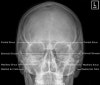

5. Adult Sinuses - PA 15 Caldwell